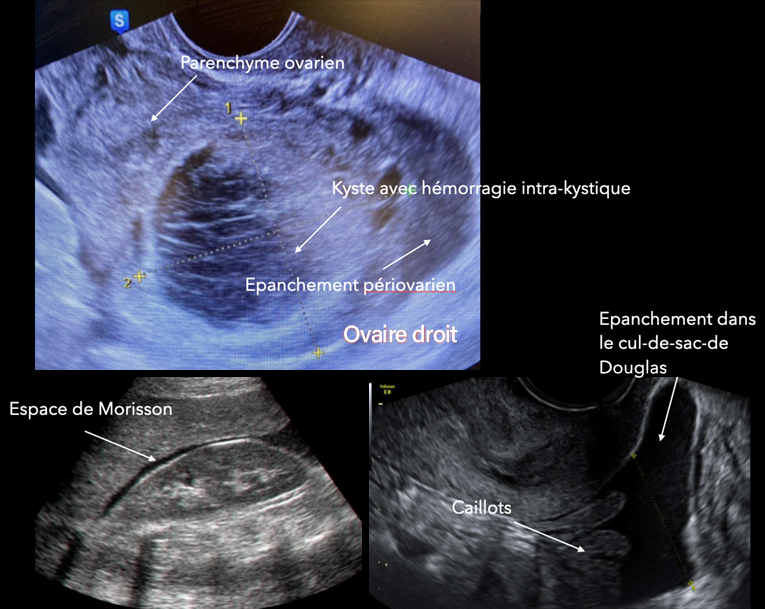

L’échographie pelvienne est la suivante (fig. 4).

Figure 4 (Rodolphe Matias de Sousa, La Revue du Praticien)

Question 6 - Quelle est votre interprétation (une ou plusieurs réponses exactes) ?

Cliniquement, l’hypotension, la tachycardie et les vertiges doivent faire évoquer un saignement actif. À l’échographie, il y a en effet un épanchement abondant dans le cul-de-sac de Douglas remontant jusqu’à l’espace de Morrison.

La douleur brutale post-rapport sexuel, l’instabilité hémodynamique, l’aspect d’hémorragie intra-kystique avec cet aspect hétérogène « en toile d’araignée » du kyste et l’hémopéritoine doivent faire évoquer une rupture hémorragique du kyste.

L’instabilité hémodynamique et le caractère probablement encore actif du saignement impose une cœlioscopie exploratrice en urgence.